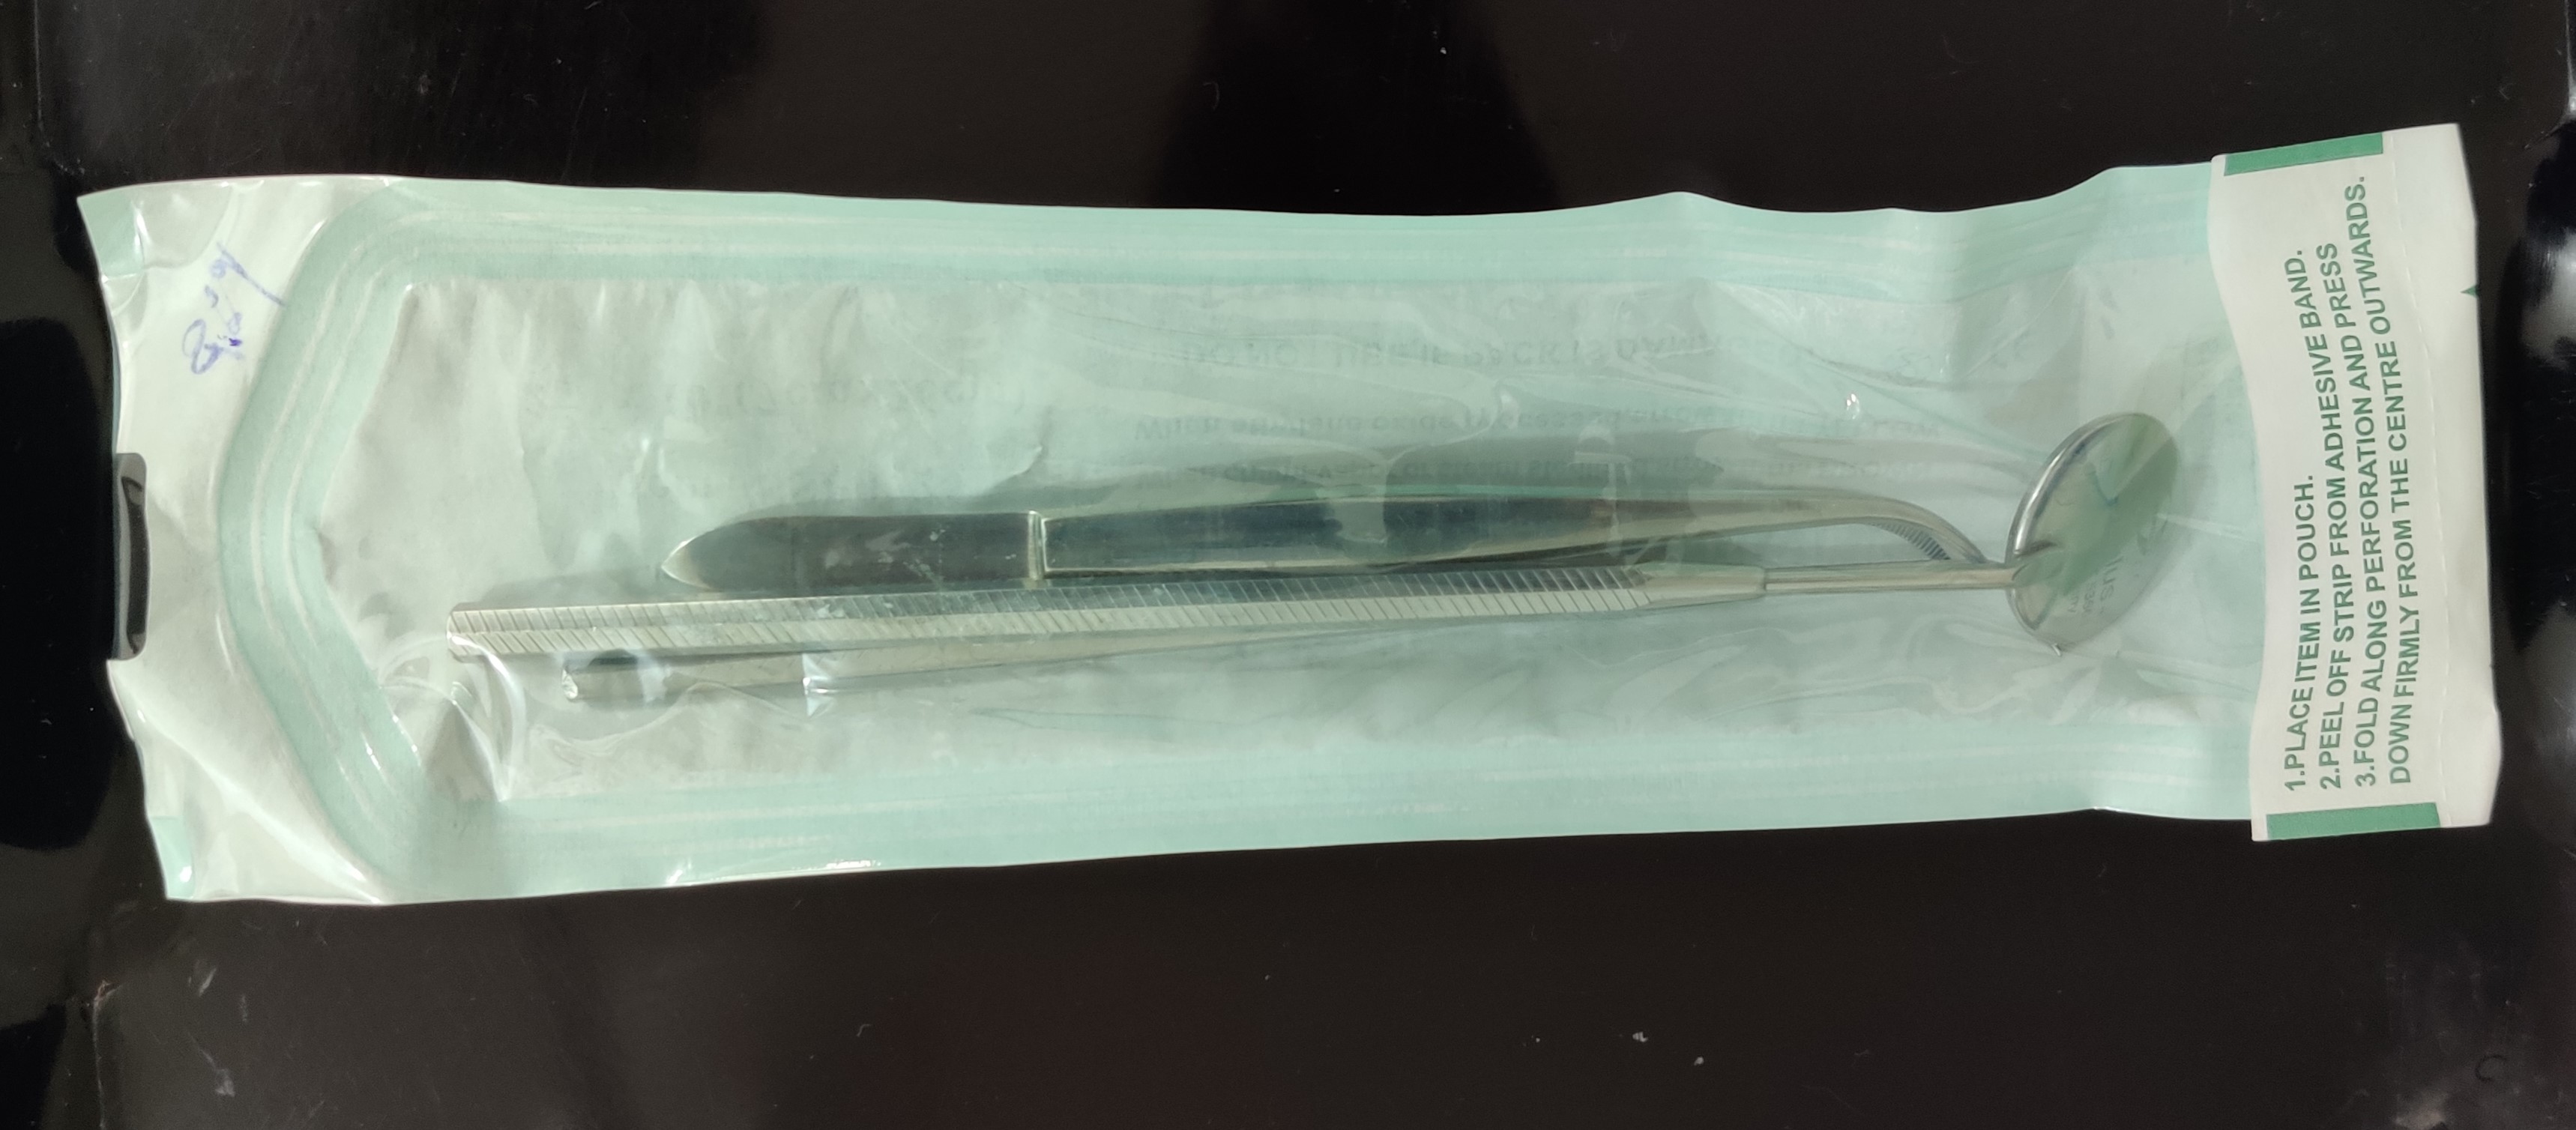

Wash The Instruments

Sealed and sterilized (In Class B Autoclave) at 121°C at 15 psi pressure for 20 minutes.

Ready For Use